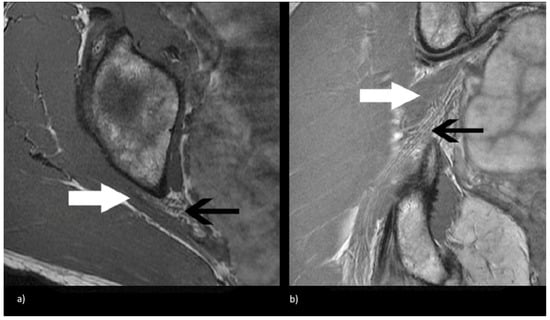

Figure 2.

Magnetic resonance neurogram (MRN) of non-split sciatic nerve (type I). (a) Axial T1-weighted MRN of the sciatic nerve at the level of the sciatic notch demonstrates normal sciatic nerve (black arrow) anterior to the piriformis (white arrow). (b) Coronal T1-weighted sequence showing type I sciatic nerve (black arrow) inferior to the piriformis (white arrow).

Beaton and Anson originally described six anatomical relationships between the sciatic nerve and piriformis muscle, as shown in Figure 1 [5]. Type I describes the conventional and most common relationship, in which an undivided sciatic nerve courses anterior and inferior to the piriformis muscle, visualized in Figure 2. Cadaveric studies demonstrate the prevalence of type I nerves to be approximately 87% [6,7]. The remaining 13% display variant anatomy, with the overwhelming majority of these characterized by the common peroneal nerve component running through a bifid piriformis muscle, and the tibial component remaining in the conventional location, inferior to the piriformis (type II) [6], as shown in Figure 3. The remaining variants (type III–VI) are rare, occurring in fewer than 1% of all cases.